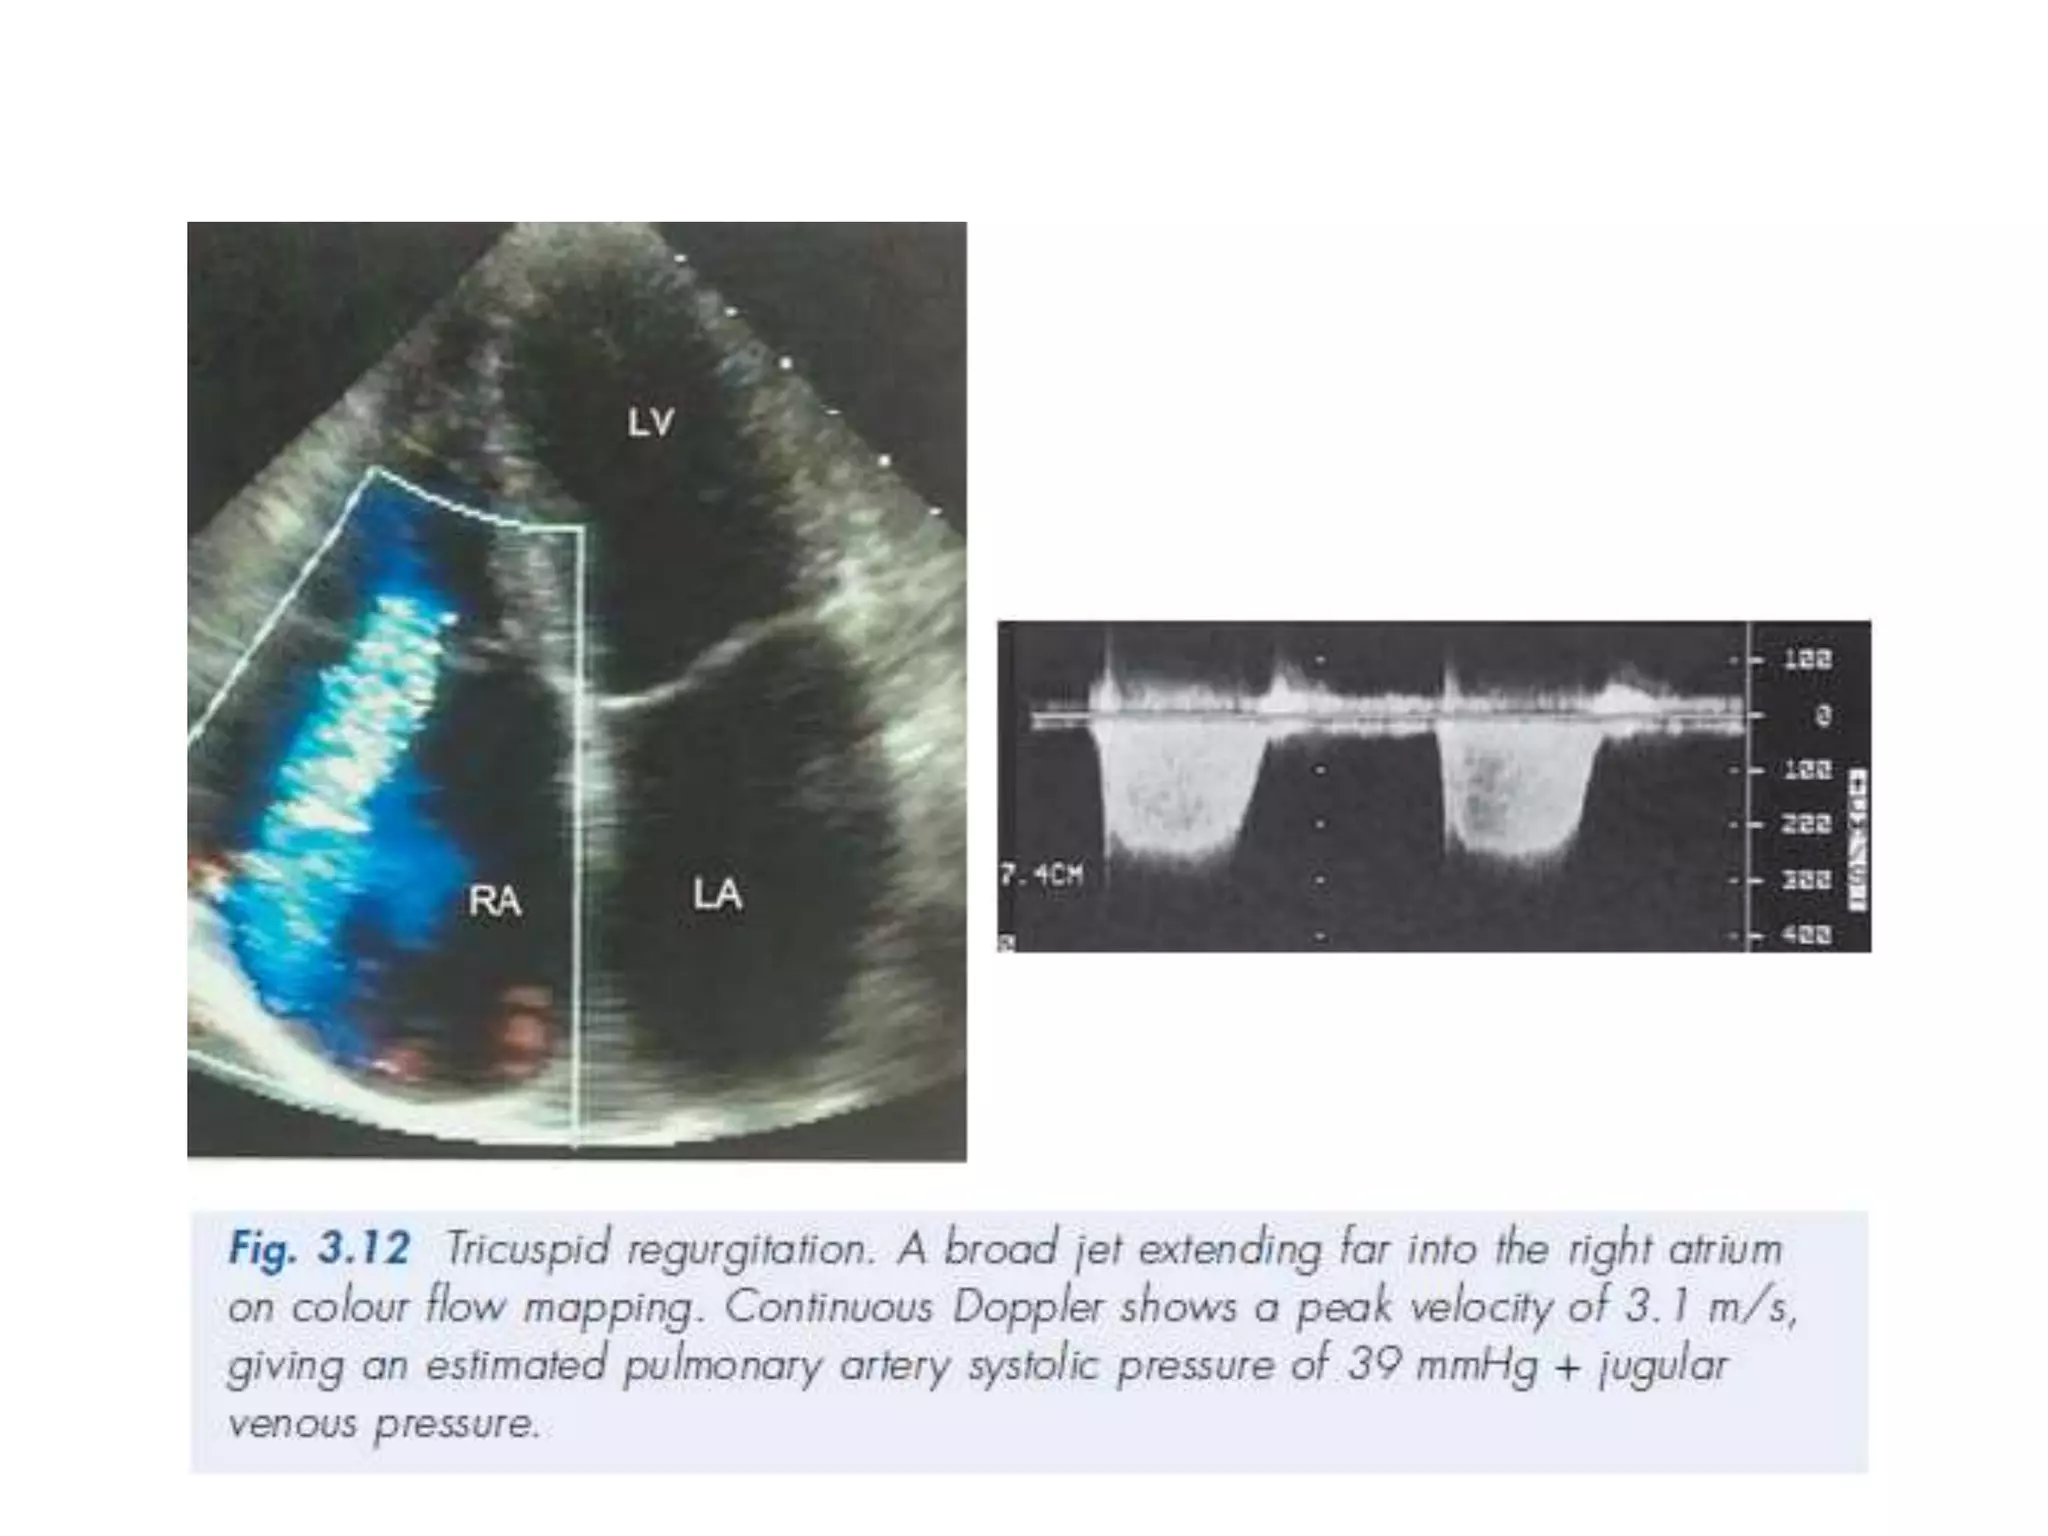

TR

Pulmonary hypertension • Thisis defined as an abnormal increase in PA pressure above: – 30/20 mmHg (normal 25/10 mmHg) – Mean 20 mmHg at rest – Mean 30 mmHg during exercise. • In those aged over 50 years, PHT is the third most frequent cardiovascular problem after coronary artery disease and systemic hypertension. • Echo is useful in assessing the underlying cause and severity of PHT, but echo examination can be technically more difficult since many of these individuals have underlying lung disease. This is especially true if the lungs are hyperinflated or there is pulmonary fibrosis.

The echo featuresof PHT M-mode – Abnormal M-mode of the pulmonary valve leaflets with absent A-wave or mid-systolic notch – Dilated RV with normal LV – Abnormal IVS motion (‘right ventricularization’ of IVS) – Underlying cause, e.g. MS (PA systolic pressure is an index of severity).

• 2-D echo –Dilated PA (e.g. parasternal short-axis view at aortic level). The PA diameter should normally not be greater than aortic diameter – RV dilatation and/or hypertrophy – RA dilatation – Abnormal IVS motion – Underlying cause, e.g. MV or AV disease, ASD, VSD, LV dysfunction. • Doppler – This is the best method to assess PA systolic pressure using TR velocity (as described in Ch. 3), or short PA acceleration time as a surrogate of PHT.